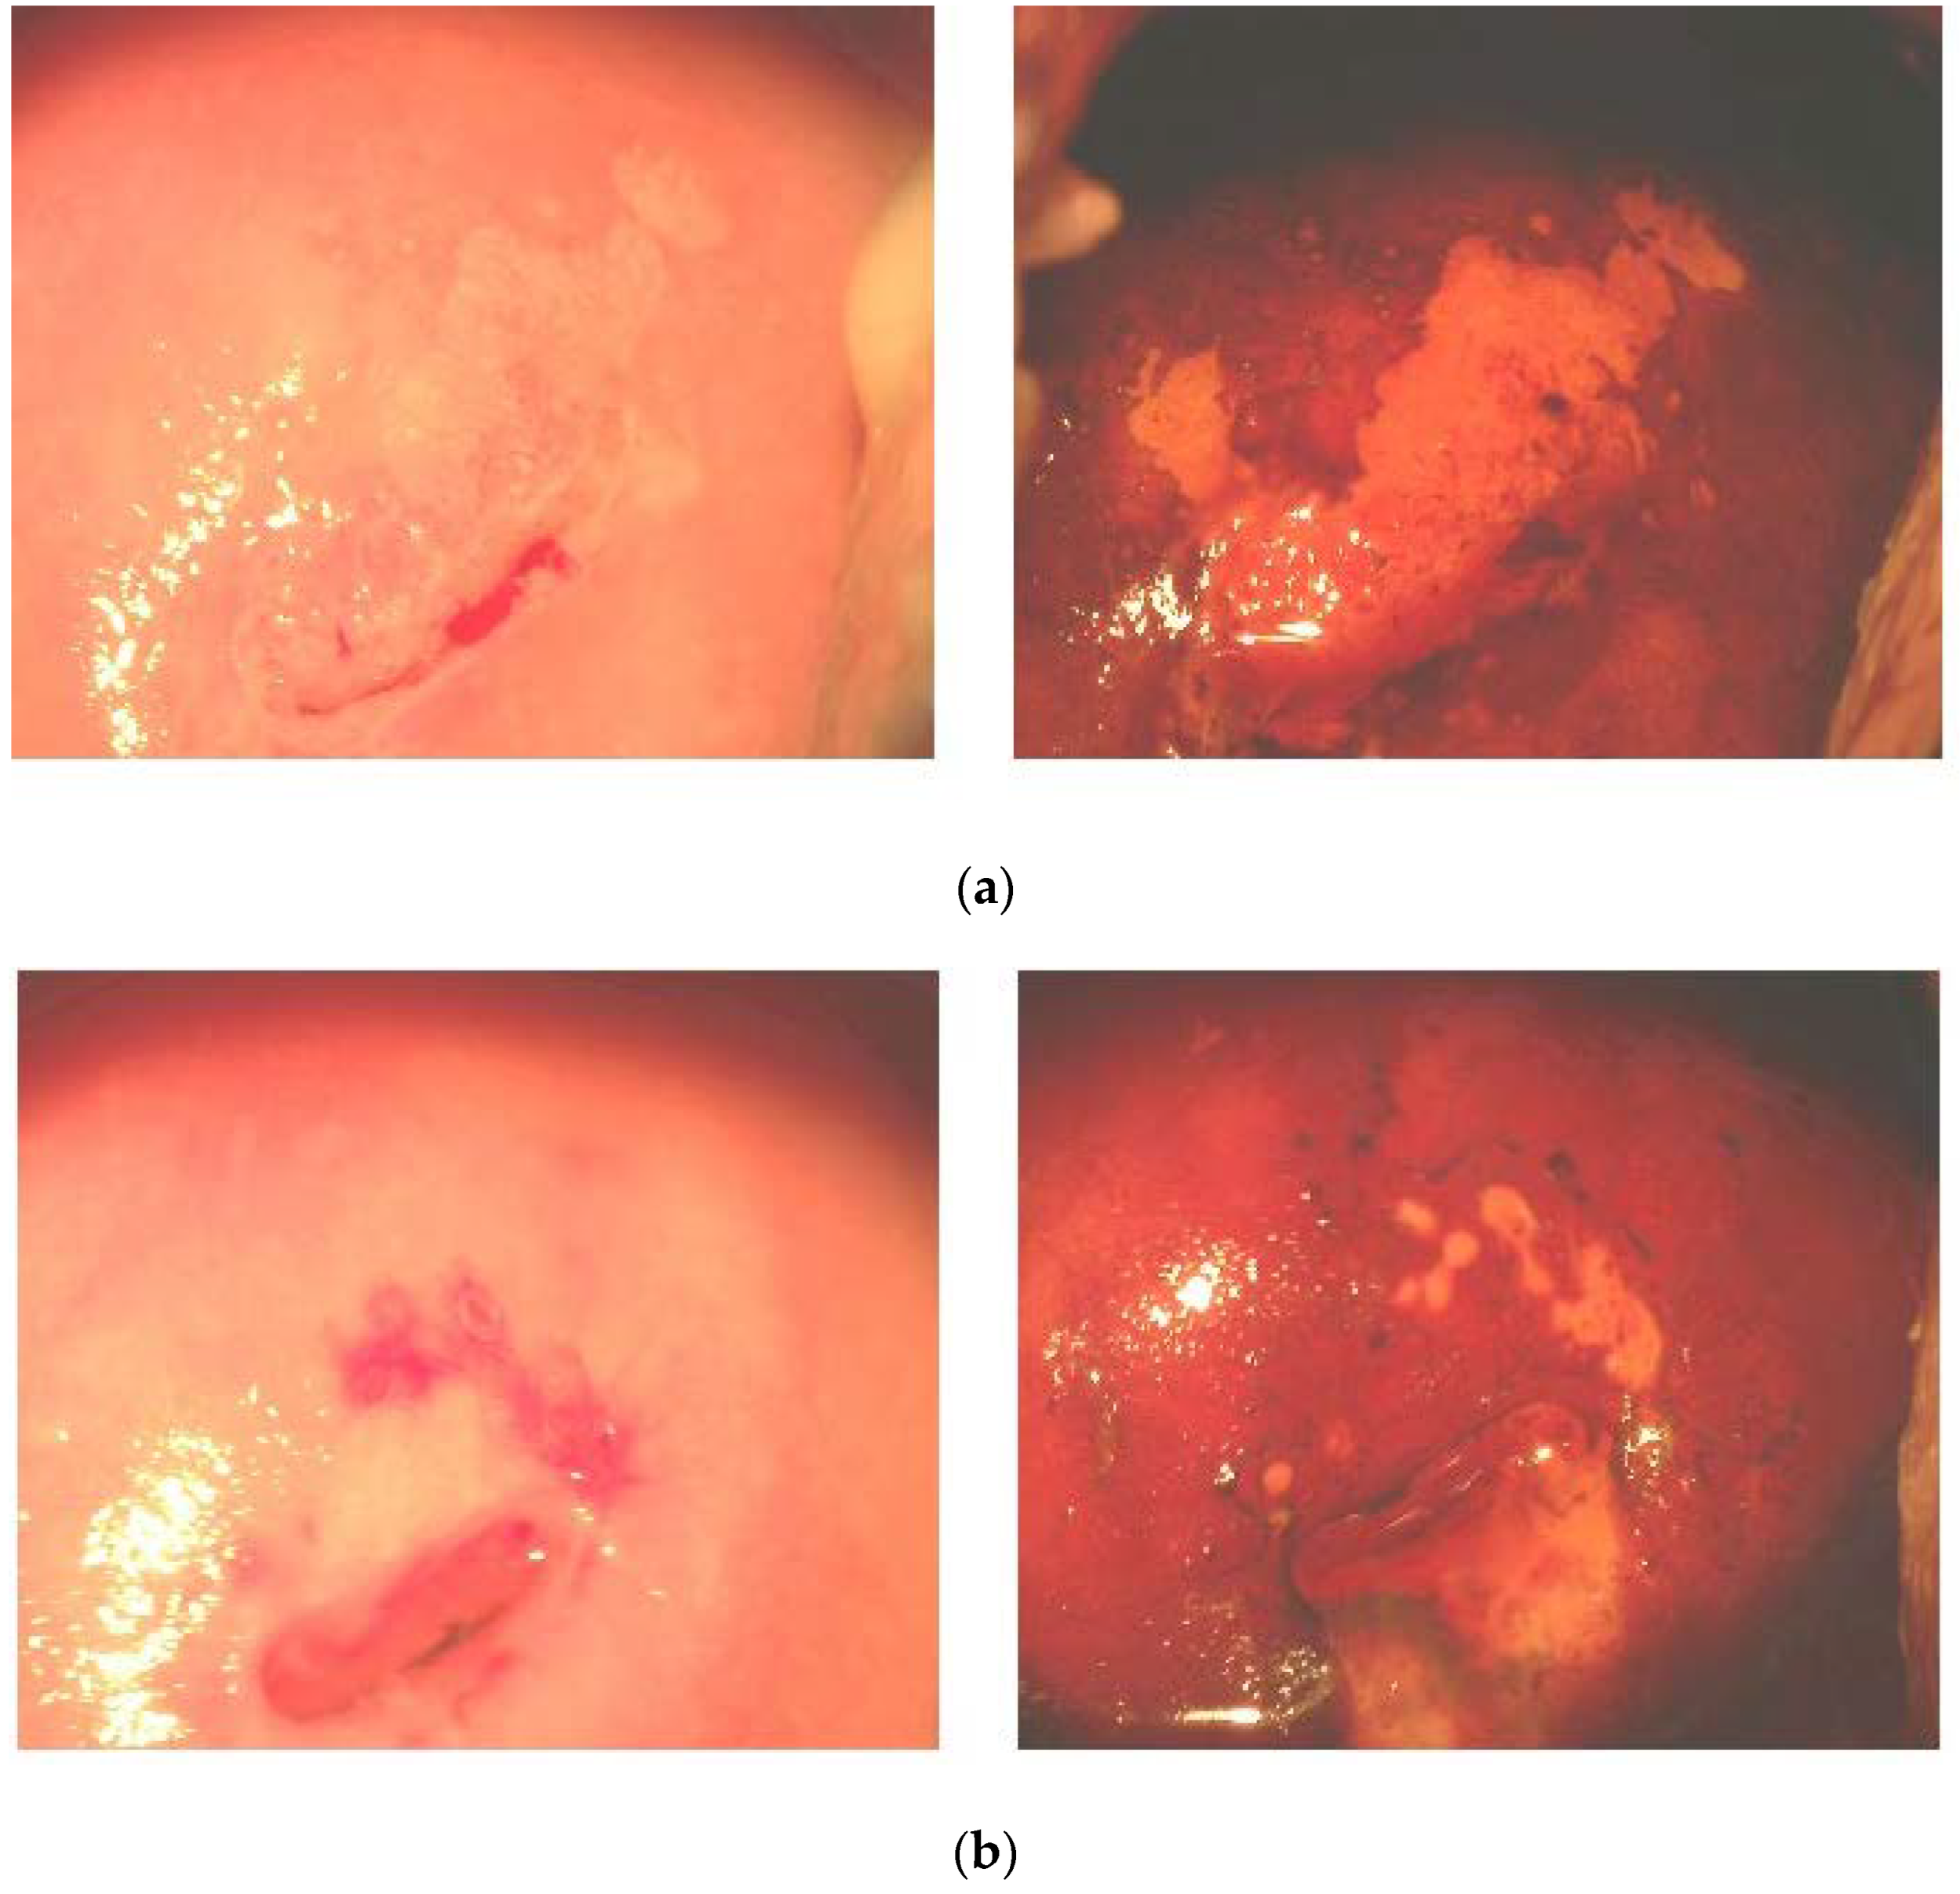

The post-trial colposcopic examination revealed normal patterns in 100% of the FM group versus 62% of the placebo group. A sample of macro-histological effects of FM supplementation is shown on Figure 5, where the (a) panel photos were taken in the beginning of the trial, and the panel (b) photos were taken at the cessation of it. Before the administration of FM, ectopic transformed areas, squamous cell metaplasia, and mosaics marked by the iodine-negative areas were evident. After a three-month course of FM, we observed normal tissue basis, the shrinkage of iodine-negative areas, and cervical coagulation. Inflammatory cells in cervical fluid were found in 21% of the FM group versus 40% of the placebo group.

Figure 5.

Typical colposcopy of CIN I and CIN II lesions before (a) and after (b) administration of antioxidants. (a) Before administration of antioxidants (ectopic transformed areas, squamous cell metaplasia, and mosaics marked by the iodine-negative areas). (b) After a three-month course of antioxidants (normal tissue basis, shrinkage of iodine-negative areas, and cervical coagulation). Left panels are colposcopic images without iodine staining. Right panels are colposcopic images after iodine staining.